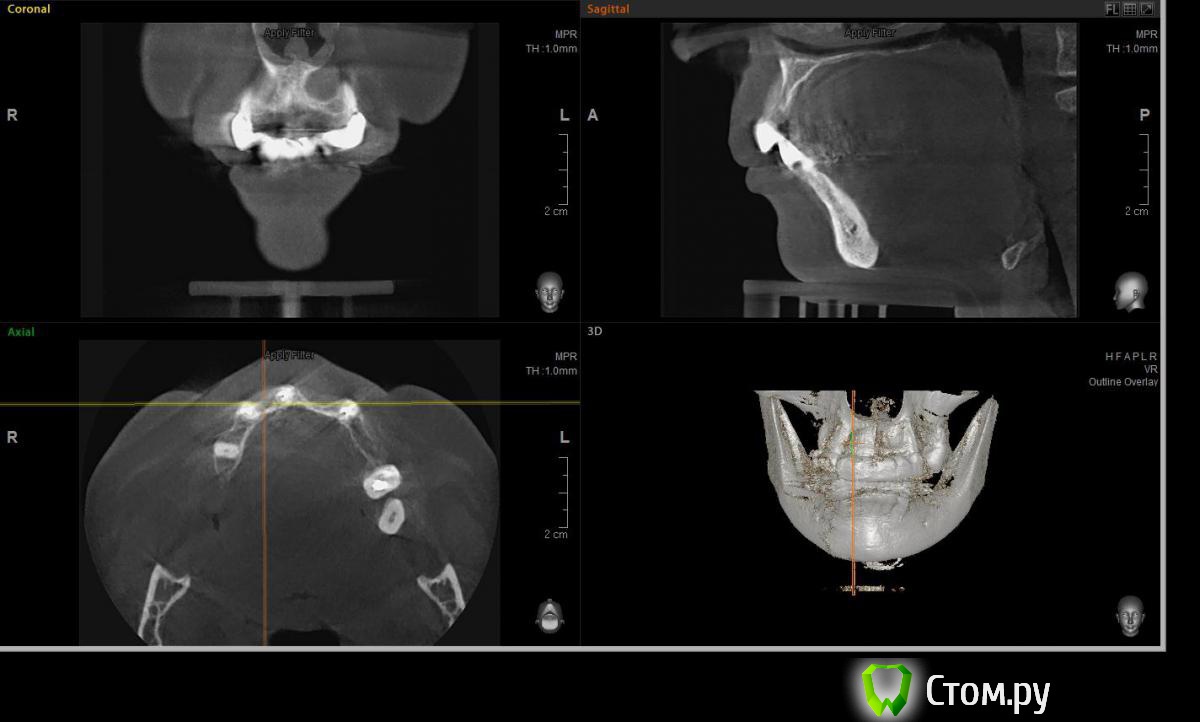

Евгений Ходыкин Опубликовано 23 июля, 2014 Поделиться Опубликовано 23 июля, 2014 Решили с пациенткой пока начать с в.ч. В планах имплантация в область отсутствующих 1.6, 1.4, 1.2, 2.1, 2.2, 2.4, 2.5. С 1.6 самому более менее все понятно, мануальных навыков хватит) Прошу помощи коллег относительно остальных областей. Фронт особливо печален... Забегая наперед скажу, что блоки еще не делал. Ауто точно пока брать не планирую, ибо нет даже теоретических навыков. Хочу начать все-таки с аллоблоков. У кого какие будут мнения, заранее спасибо) Ссылка на комментарий

Rafael_Gogyan Опубликовано 24 июля, 2014 Поделиться Опубликовано 24 июля, 2014 (изменено) фронт блоклибо сосиску (минимум 50% ауто) с одномоментной имплантациейв боковых отделах особых проблем не вижу. имплантация с НТР в обеих случаях + ССТ на ножке с нёба Изменено 24 июля, 2014 пользователем Rafael_Gogyan Ссылка на комментарий